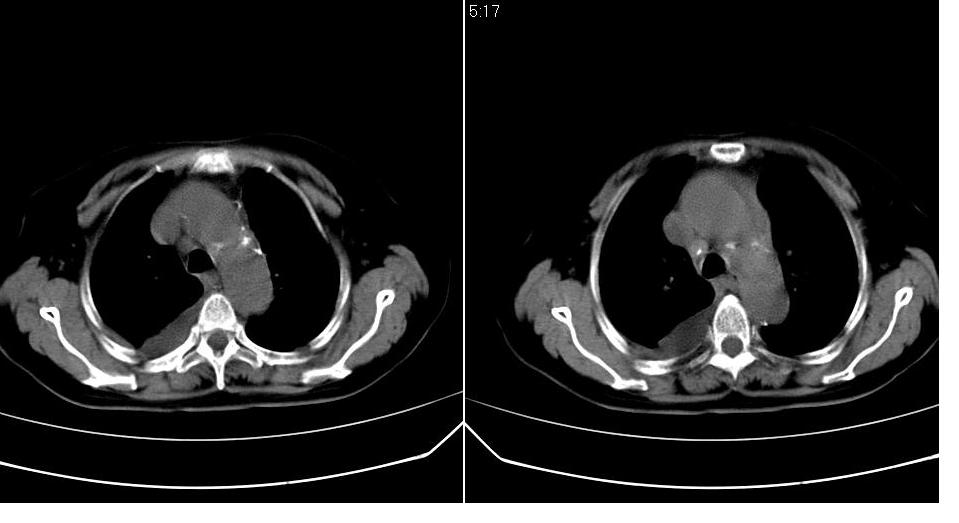

以下是引用zhangzhongshou在2007-7-11 13:16:00的发言:[br]1、冠状动脉钙化[br]2、心包积液[br]3、右侧胸腔积液[br]大家都考虑心衰,冠状动脉钙化、肺纹理增强,胸腔积液、心包积液,表面上是支持,但是为什么右侧有较多积液,左侧没有呢? 如果用结核性胸膜炎,并结核性心包炎也可解释,请楼主进一步提供临床资料。

以下是引用zrs在2007-7-11 14:40:00的发言:[br]支持心衰,心衰所至的胸腔积液常常是右侧多

以下是引用liaizhi在2007-7-11 15:41:00的发言:[br]两肺纹理增粗,肺门影增大,气管支气管通畅。升主动脉壁及冠状动脉壁钙化。左房左室稍扩大。心包积液,胸腔积液。考虑冠心病并心功能不全,肺水肿,胸腔积液。